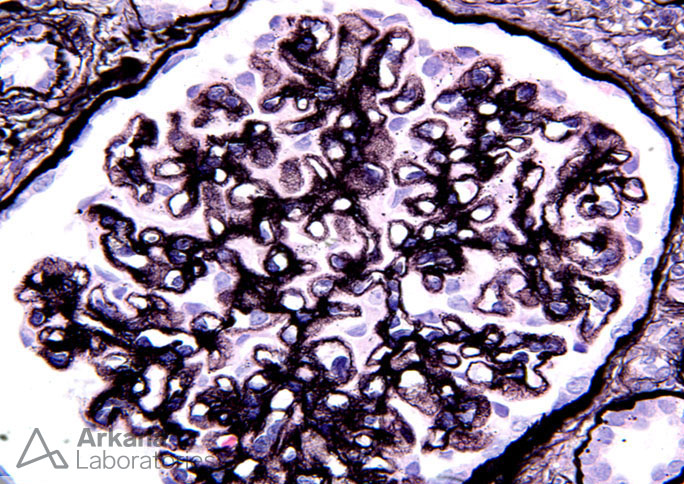

Previous Image Next Image Hole and Spike Formation in Membranous Glomerulopathy on Silver Stain_2 Like Loading...